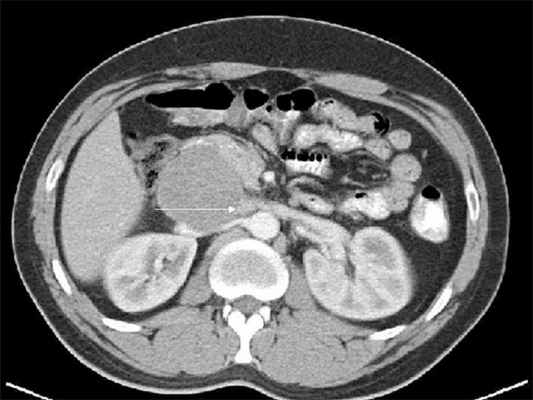

(Слева) КТ с контрастированием, аксиальная проекция: гидроуретер и контрастируемое метастатическое поражение в левой поясничной мышце.

(Справа) КТ с контрастированием, аксиальная проекция: у Этого же пациента визуализирован контрастируемый метастаз, блокирующий левый мочеточник. Видны левая общая подвздошная артерия и вена, а также левая семенная вена. Для сравнения показан нормальный правый мочеточник.